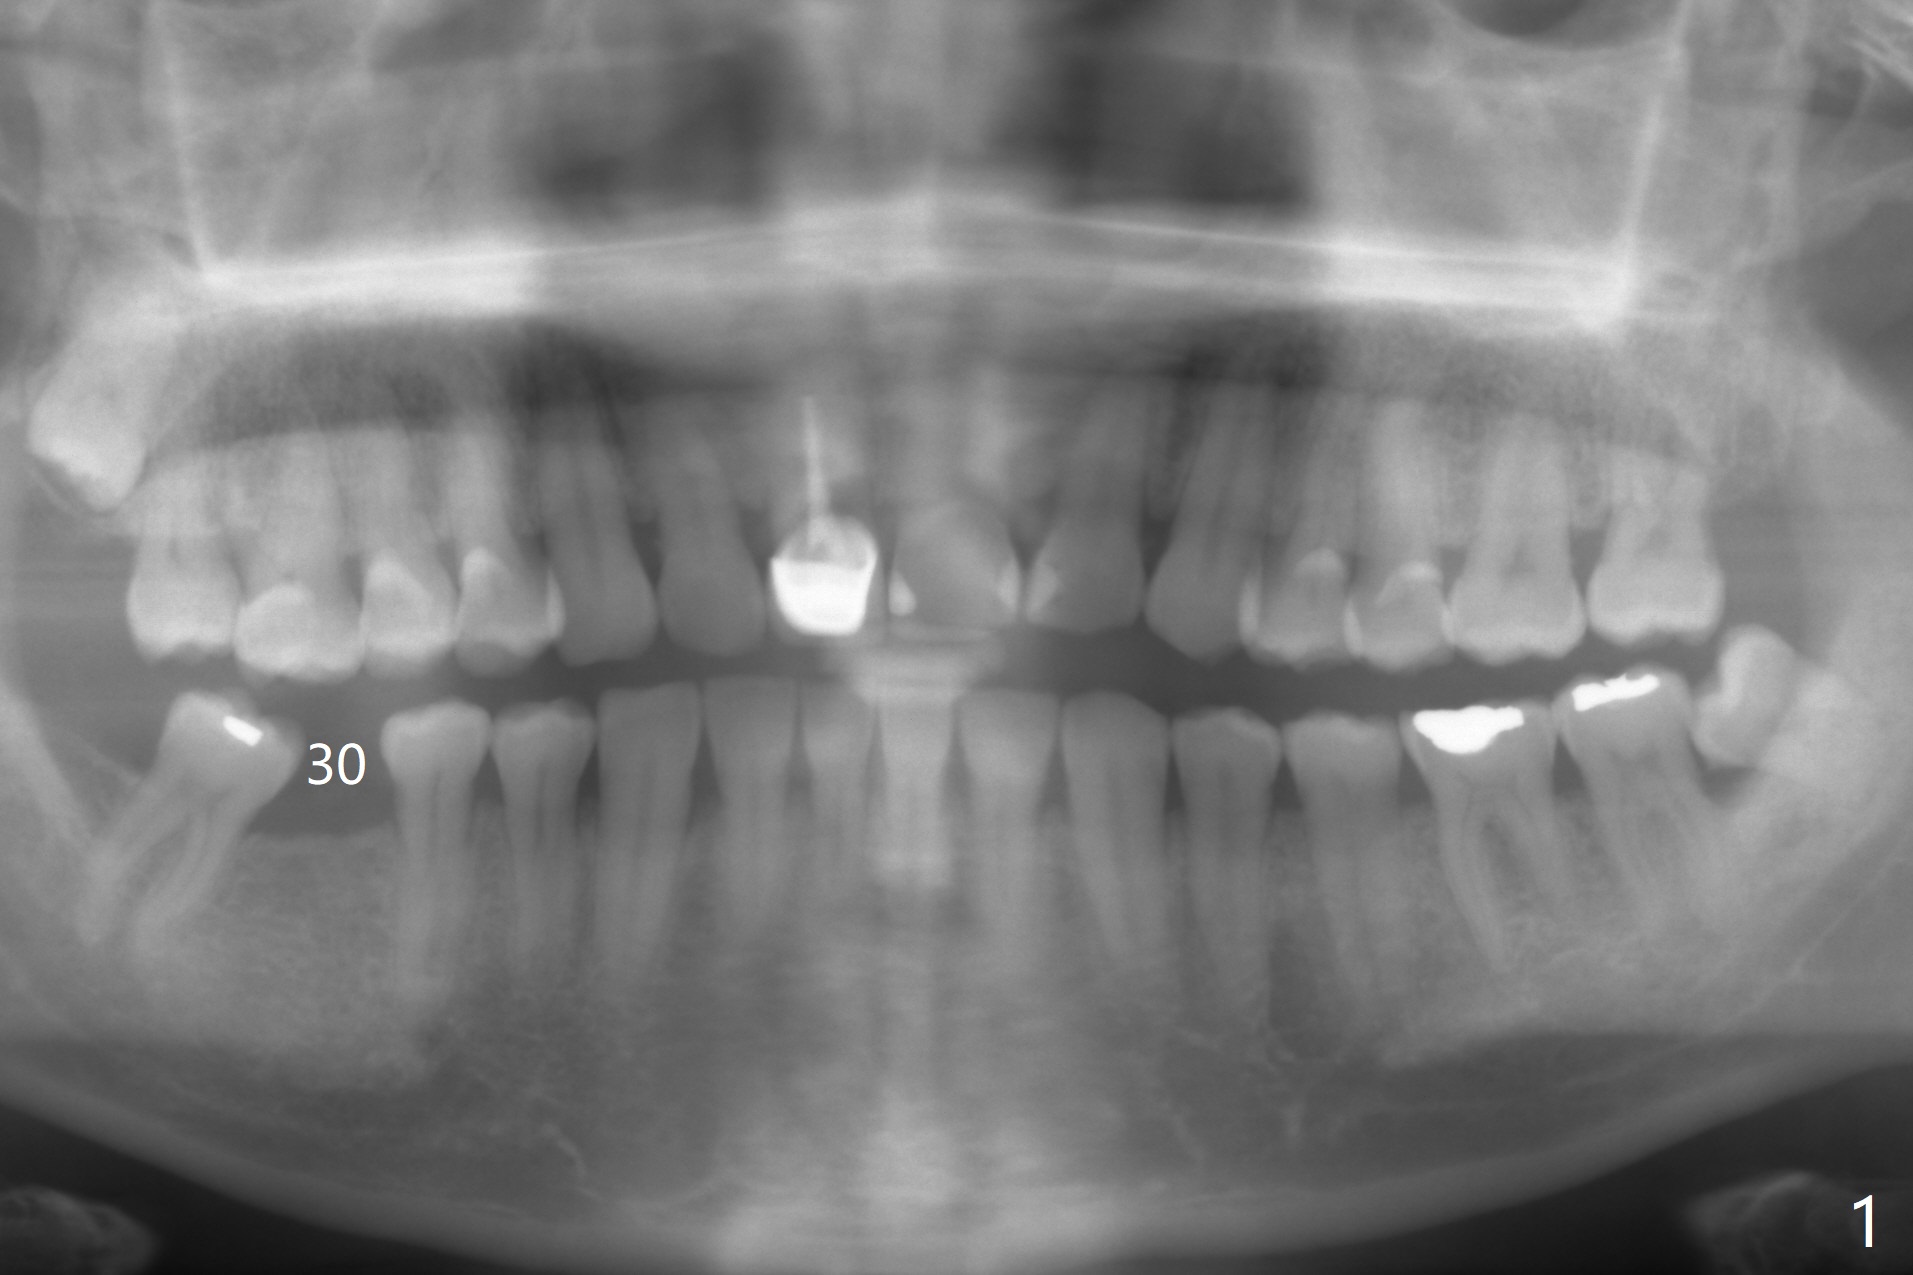

A 54-year-old man appears to be a unilateral masticator because of missing #30 (Fig.1). The left central incisor seems to have root fracture (Fig.2). To counter heavy occlusal force, a long implant will be placed (Fig.2,3).